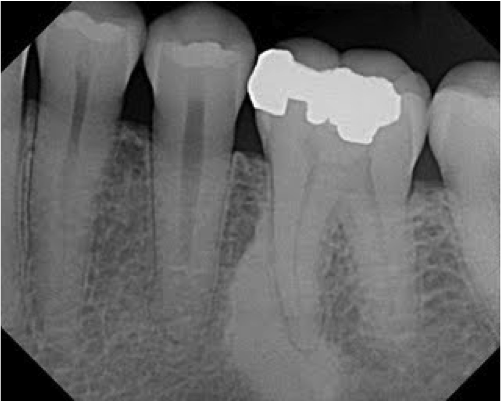

What is this? (hint: no hx of infection)

Idiopathic osteosclerosis

What is this?